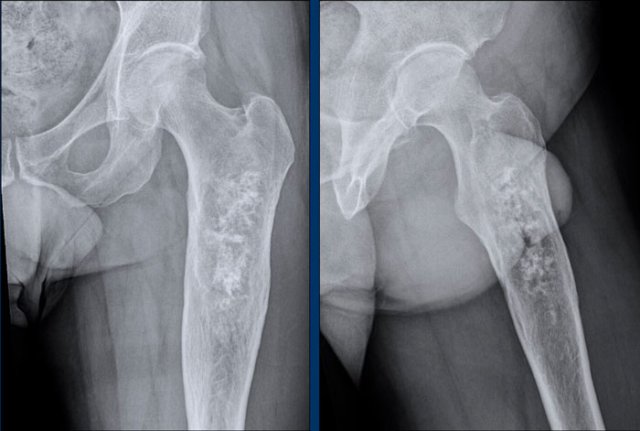

Images

There is a well defined

osteolytic lesion >10 cm in the proximal femur diaphysis with popcorn i.e.

chondroid matrix calcifications.

There is expansion of the bone, however no frank cortical scalloping or periostitis.

Conclusion

Based on the radiograph alone, this tumor could be an ACT or a chondrosarcoma of higher grade. The next step is to perform MRI for further characterization.

Case

First look at the images.

Then continue reading.

MRI confirms the chondroid nature of the tumor with hyperintense

cartilage nodules on T2 DIXON that show septonodular enhancement after

contrast.

However, there is also marked bone marrow oedema proximally (black arrow) and a periosteal reaction with enhancement (white arrow).

These features are very suspicious for the diagnosis of a high

grade chondrosarcoma.

Axial T1 weighted image confirms deep

anterior cortical scalloping over approximately 1/3 of the cortex, i.e. extensive scalloping ( > 10% of tumor circumference).

A proximal femur resection

was performed.

Final diagnosis: chondrosarcoma grade II